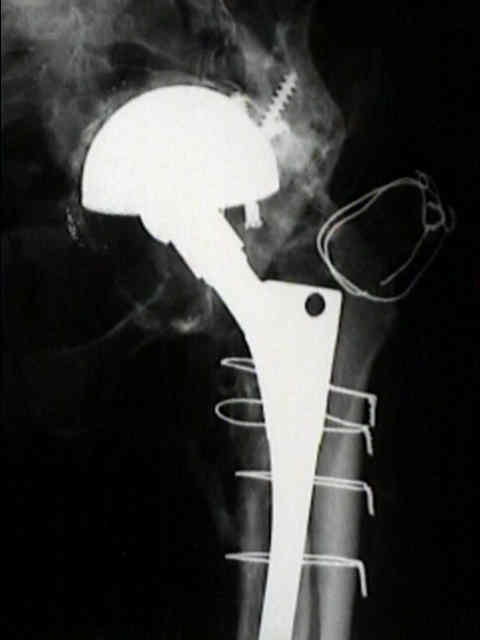

Loosening of Press Fit Acetabular Components

(press fit acetabular components)

radiographic signs of loosening

- migration

- loosening is present w/ more than 2 mm of migration (either horizontal or vertical);